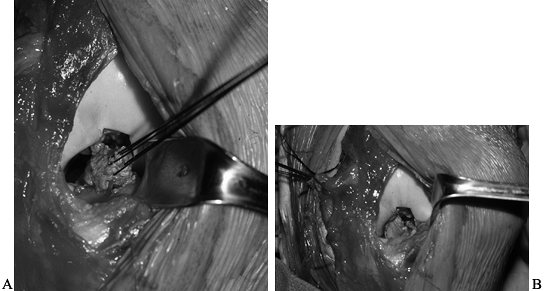

component. This occurs when one element of the supporting structures

by closed methods (8,23) (Fig. 91.5A, Fig. 91.5B).

Reduction of this dislocation can be blocked by a buttonhole tear in

the medial capsule, trapping the medial femoral condyle (Fig. 91.5C, Fig. 91.5D). This can result in a medial cutaneous skin furrow (35).

This sign is an indication for immediate open reduction; delay may

result in skin necrosis or further neurovascular compromise.

![]() |

Figure 91.5. A: Anteroposterior radiograph of a posterolateral dislocation with marginal patellar fracture. B: Lateral radiograph of a posterolateral dislocation. C: Appearance of knee before reduction. D: Medial femoral condyle buttonholed through medial capsule, blocking closed reduction.